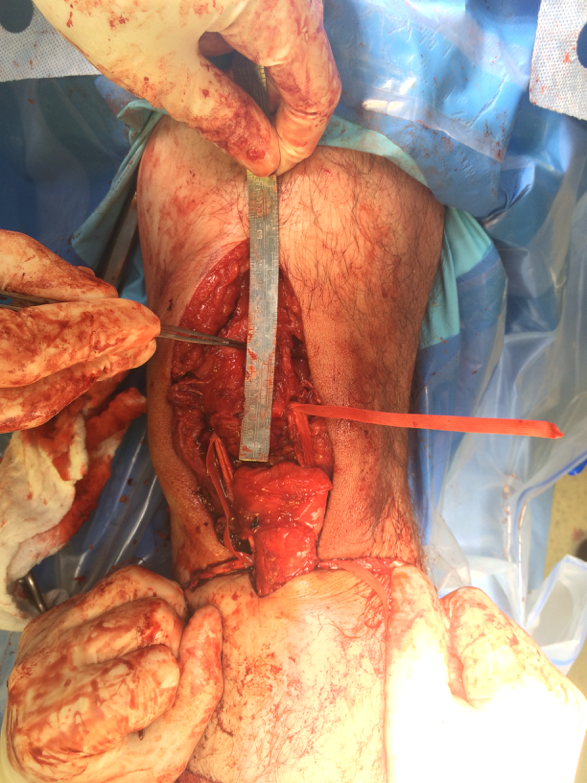

2. Avulsion from tibial tuberosity

Repair with suture anchors

3. Midtendon rupture

May need augmentation with hamstring tendon

Augmentation

1. Semitendinosus autograft

- leave semitendinosus attached distally

- pass through distal pole patella

- reattach to tibia on lateral side

2. Patella tendon Allograft

3. Lars Ligament

Chronic Rupture

Reconstruction

Case: Reconstruction with tendoachilles allograft, bone block in tibia

Case: Reconstruction with Hamstring Autograft (if patella relatively low) or Tibialis Posterior